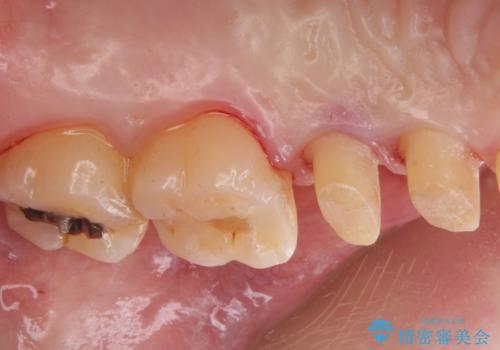

拡大鏡下で銀の詰め物、古いプラスチックの樹脂を外し、虫歯が残ってないかを確認して

ジルコニアクラウンで治療を行いました。

白い被せ物を入れたことにより銀が目立たなくなり

染みることもなくなりました。

ご希望に沿った治療となり大変満足して頂けました。